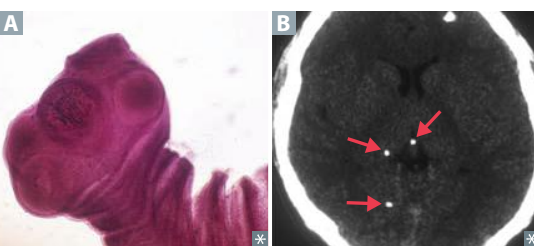

Taenia solium–disease

Taenia solium–transmission of Cysticercosis, Neurocysticercosis

Taenia solium–treatment of cysticerosis, neurocysticercosis